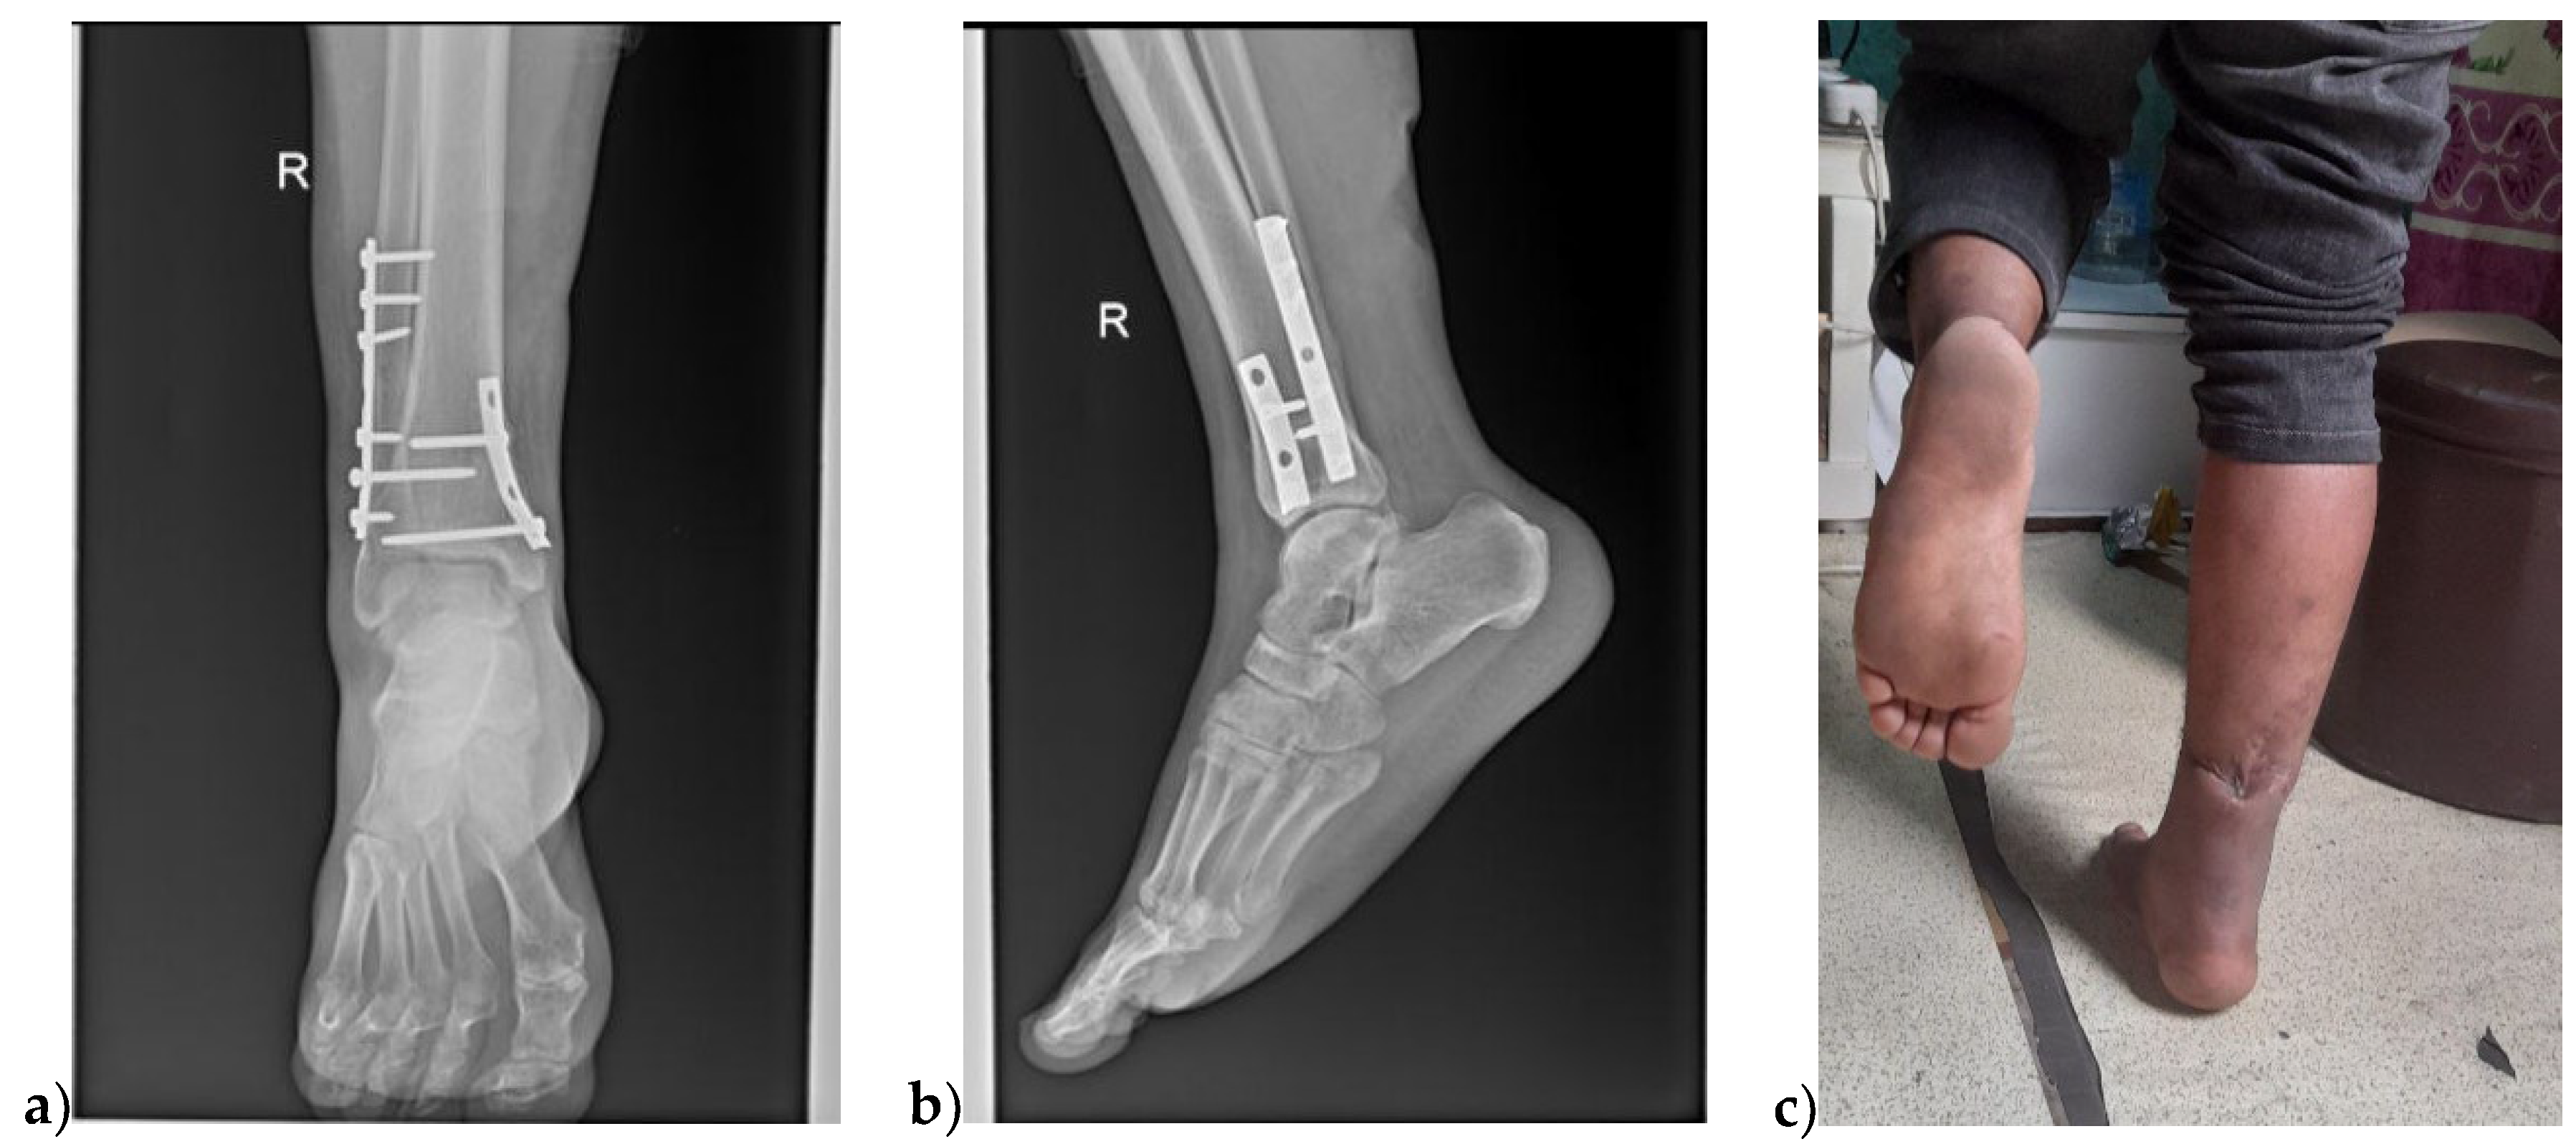

X-ray images were taken on the following day and showed a bimalleolar ankle fracture; vertically oriented non-displaced medial malleolar fracture and supra-syndesmotic lateral malleolus fracture (Figure 2).

We discharged him on his 7th post-op day with 200 plantarflexed foot. At 2 weeks postoperatively, the wound sites were healed and suture materials were removed. At 6 weeks control X-ray was taken and showed the bimalleolar fracture was healing and active range of motion exercise started with a hinged ankle-foot orthosis. At 12 weeks the fracture consolidated and the patient was allowed full weight-bearing with some jogging. During his 6-month postoperative time, he was completely asymptomatic and able to perform single-legged heel raise exercises(Figure 5).

Figure 5. Functional outcomes at 6 month post-op; a & b) Ap and latera X-ray of healed bimalleolar fracture, c) single legged stance at 6 month post-op.